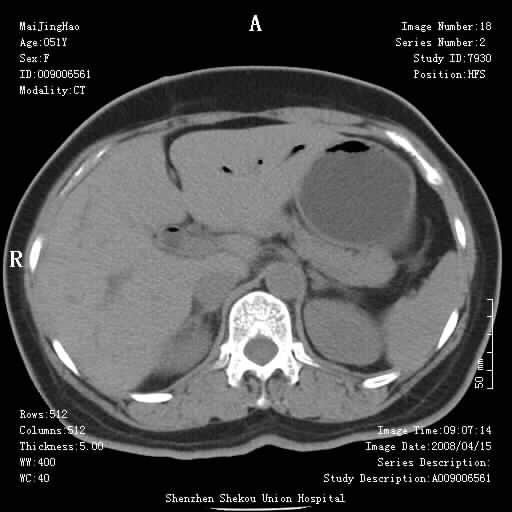

以下是引用余辉在2008-4-26 8:55:00的发言:[br]患者有结石史,此次腹痛4小时,胆总管全程扩张,应有胆总管末端梗阻,此次仍考虑胆结石症,积气不外两种原因,一种是结石下移时肠道内气体逸入,其次为产气菌感染。(倒数第三幅图像于扩张之胆总管末端似可见稍高密度影,考虑为结石影)

以下是引用听蝉观竹在2008-4-26 11:41:00的发言:[br]胆道手术分两种情况:[br]1、如果仅仅做胆囊切除手术,肝内胆管不会积气,只会出现胆总管代偿扩张,因为奥迪氏括约肌依然功能正常胆道与外界并不相通;[br][br]2、胆囊切除+胆总管空肠吻合手术(即roux-y式),则肝内胆管会出现积气,只是因为胆管与小肠相通,气体来源于小肠。这是临床十分常见的手术。[br][br]这个病例应该是胆囊切除+胆总管空肠吻合手术,是正常手术后表现,并不是胆道感染的表现。